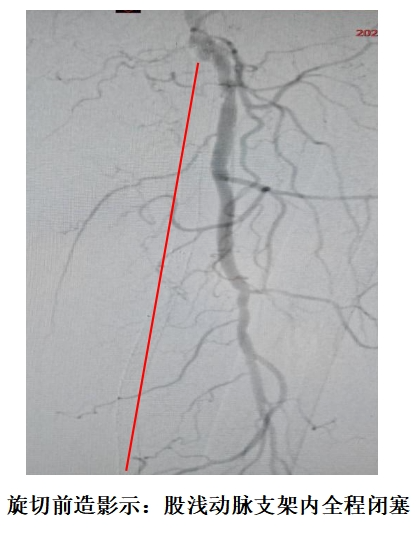

血管介入科手术团队密切配合,通过股动脉穿刺,将2.4mm旋切导管送至闭塞段,采用Blades Down模式旋切钙化斑块2次,再以REX模式抽吸碎屑2次,实现“无残留”清理。术后即刻造影显示血流明显通畅,无闭塞及斑块,患者左下肢皮温回升,血供改善,次日即康复出院。